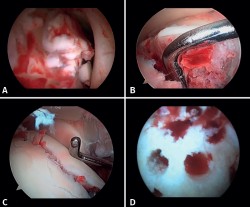

Si es posible, realizaremos la reinserción de fragmentos osteocondrales inestables (Figura 3). En las lesiones condrales donde no es posible reinsertar el fragmento, pueden emplearse técnicas de estimulación de reparación del cartílago(5,13).

Figura 3. A: cuerpos libres; B: lesión osteocondral; C: reducción de la lesión osteocondral; D: estimulación medular.